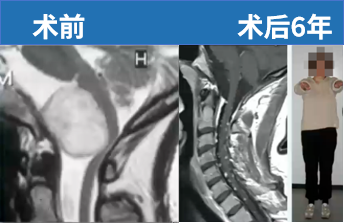

颅内脑膜瘤在所有中枢神经系统原发性肿瘤中占比约25%至40%,其中约三成是体检或其他检查时无意发现的,其余则是在肿瘤压迫邻近神经结构产生症状后才被确诊。显微外科切除术仍是目前脑膜瘤治疗的金标准。以下这一案例涉及一名33岁女性患者,因突发颈部剧痛伴身体右侧感觉异常就诊,最终诊断为枕骨大孔脑膜瘤。

该33岁女性患者接受背外侧入路手术全切肿瘤,术后6年随访无复发,神经功能状态良好,无任何神经功能损伤后遗症。